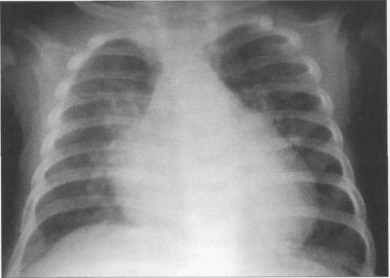

У новорожденных сердце имеет относительно большую величину, СЛК у них может достигать 58% (рис. 9.22). У более старших детей и у взрослых СЛК составляет 44—48%, для большого числа подростков характерны небольшие размеры сердца (СЛКменее 40%) (рис. 9.23),улюдей пожилого возраста поперечные размеры сердца увеличиваются, СЛК у них, как правило, более 50%.

Рис. 9.22. Рентгенограмма грудной клетки ребенка 3 месяцев. Задняя проекция.